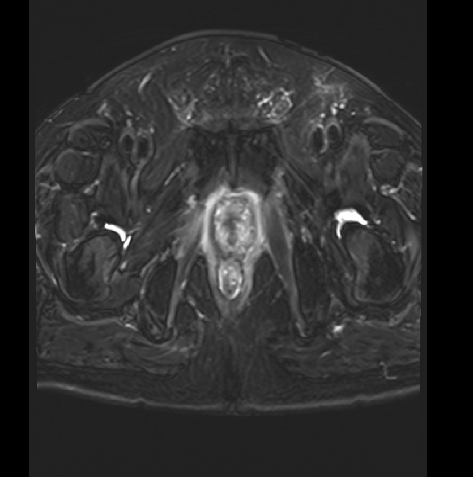

MR:1、直肠癌(T3可能),与右侧肛提肌关系密切,考虑1、炎性渗出粘连2、侵犯待排2、慢性膀胱炎3、前列腺增生。

2017-09 MR:

2018年11月:直肠壁异常信号,考虑复发

2019-06:

2020-05: